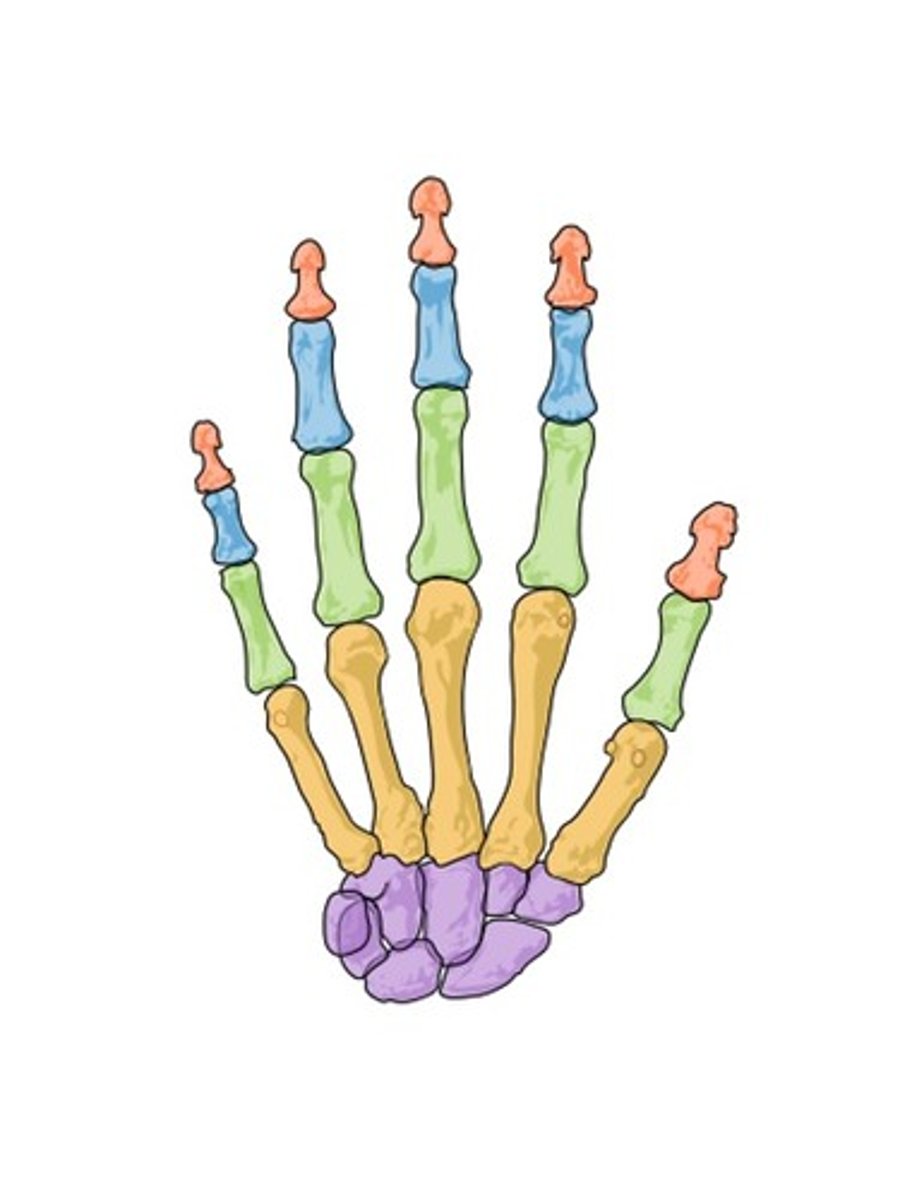

proximal phalanges

ID GREEN bones

middle phalanges

ID BLUE bones

distal phalanges

ID red bones

metacarpal

ID YELLOW bones

carpals

ID PURPLE bones